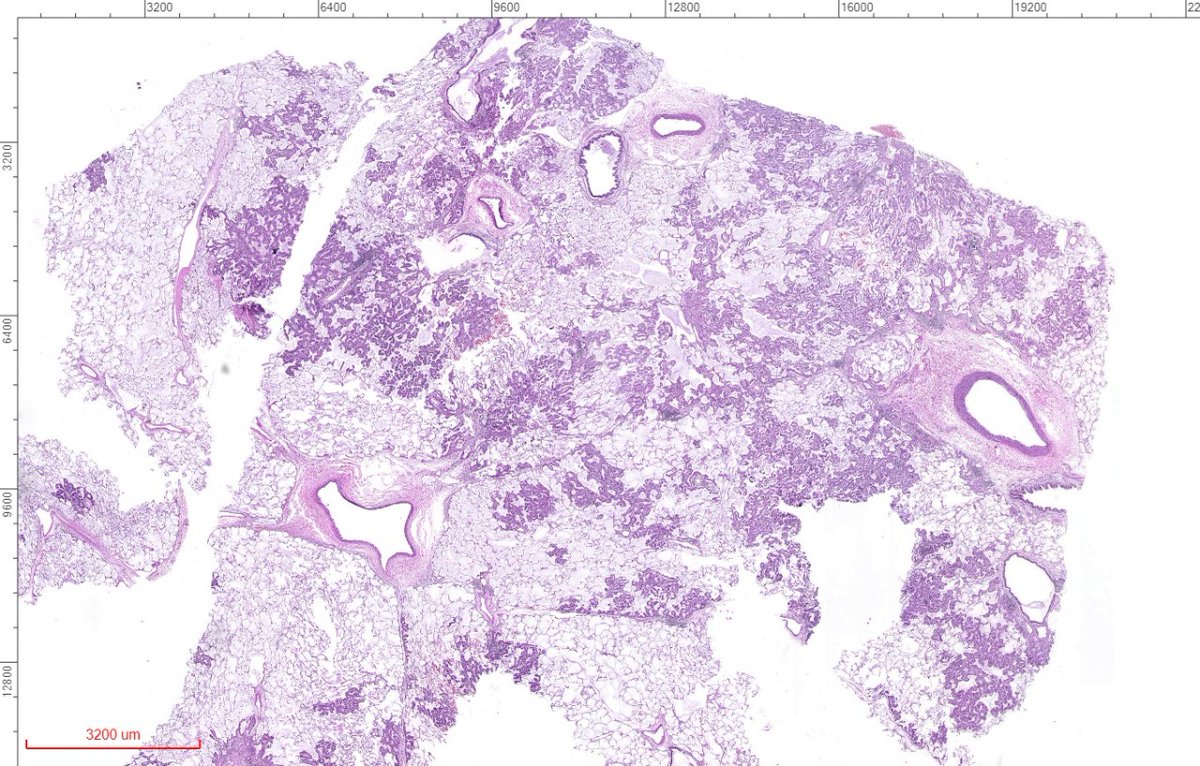

A: Lung Adenocarcinoma (in situ): Images showing emphysematous, lepidic growth pattern w/ increased presence of macrophages in the alveolar spaces, and a close-up of lepidic growing tumor cells around a blood vessel. @LungAssociation @UMRogelCancer #PulmonaryPath #DailyDX